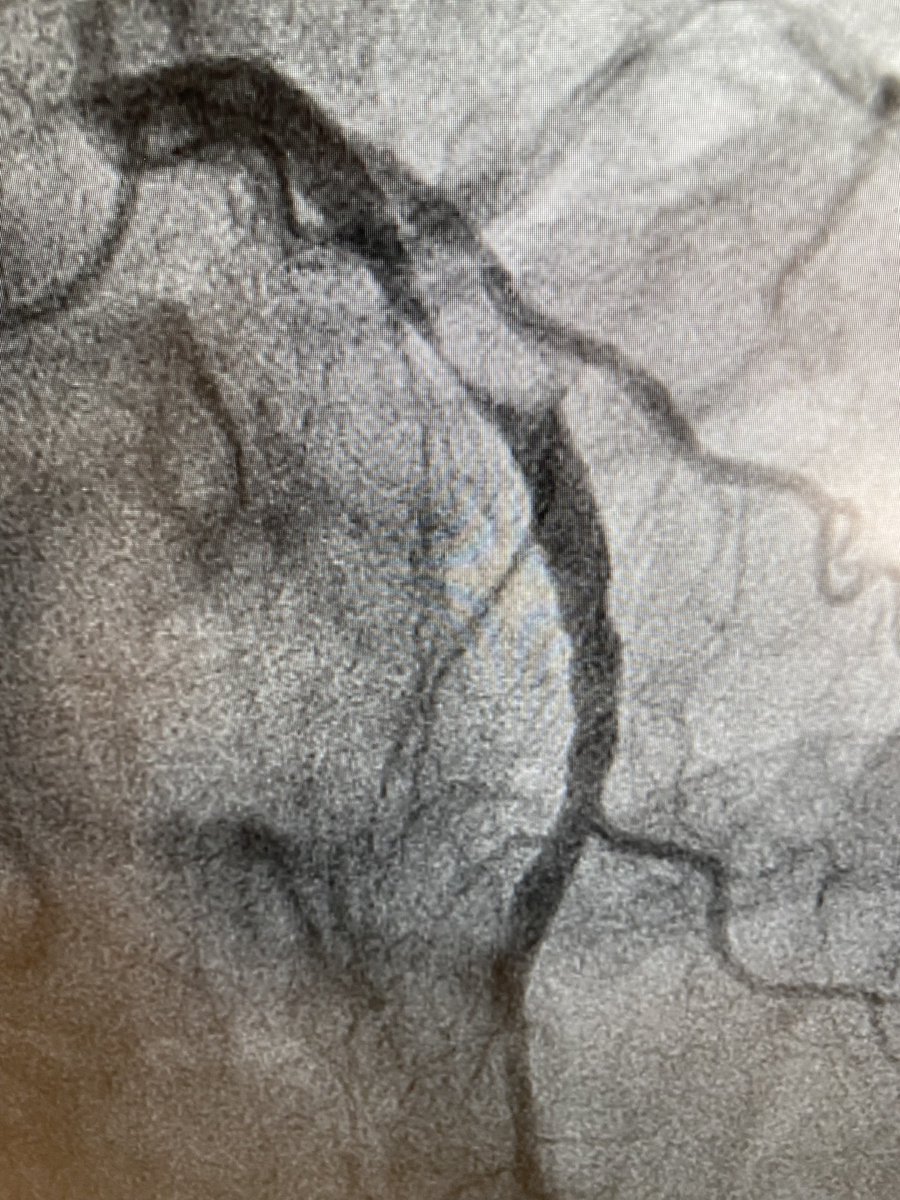

50yo nonDM👨🏻🦳 2+mo exertional angina, Trop/echo WNL. How would you manage? #CardioTwitter 🎥 on RP @mmamas1973 @SandeepNathanMD @mirvatalasnag @djc795 @SVRaoMD @rajivxgulati @Drroxmehran @DLBHATTMD @djkereiakes @BinitaShahMD @CardioNerds @DrJayMohan @richardbogle @fischman_david